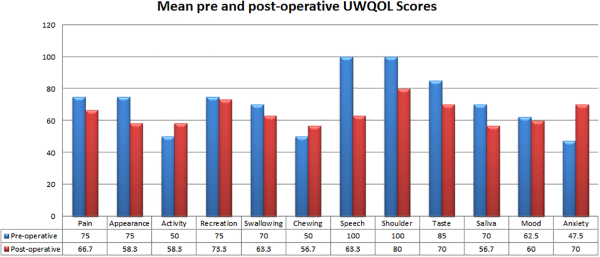

Comparison of UWQOL scores did not show any considerable difference in QOL between the pre-and postoperative period; however, small improvements were noted in activity, chewing and anxiety scores, and no change or mild reduction seen in the remaining domains (Figure 3). Similarly, mean MDADI scores did not show any substantial difference across all domains, with global and emotional scores being identical pre- and postoperatively (G 66.7 vs 66.7, E72.2 vs 72.2) and functional and physical (F 58.7 vs 60, P 56.7 vs 57.54) scores demonstrating a slight improvement posttreatment (Figure 4).

Figure 3

Graph and table summarizing mean preoperative (blue) and postoperative (red) University of Washington quality of life scores.